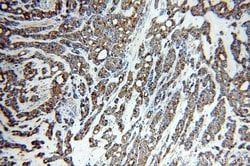

This antibody is specifically against KRT7.

Cytokeratin 7 blocks interferon-dependent interphase and stimulates DNA synthesis in cells. Involved in the translational regulation of the human papillomavirus type 16 E7 mRNA (HPV16 E7).Specifications

| Immunocytochemistry, Immunofluorescence, Immunohistochemistry (Paraffin), Immunoprecipitation, Western Blot | |